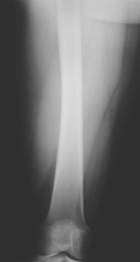

P.G. - 49 year old female presents with a two month hx of painful right thigh mass.

Zoom image: Radiological image Radiological image.